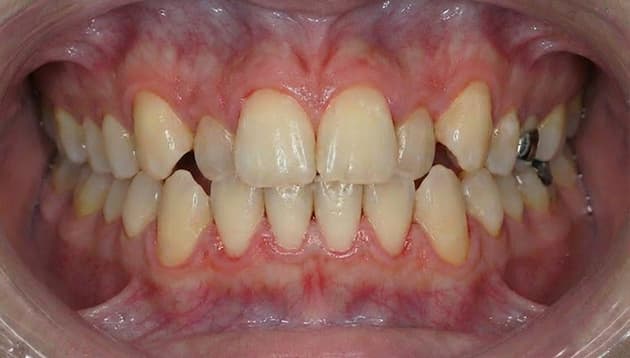

上顎部分矯正症例

- 症例について詳しく見る

-

症例名 上顎部分矯正/上の前歯のガタガタ 患者さまの主訴 小さい頃に矯正したが後戻りしてきた、上のガタガタ治したい 治療内容 上顎部分ワイヤー矯正 患者さまの年齢 36歳 患者さまの性別 男性 治療期間 5ヶ月 治療にかかった総額 33万円(税込) 治療する際に起こるメリット 治療により、見た目の改善、噛み合わせ・咀嚼機能の改善、清掃性向上(虫歯・歯周病リスク低下につながる場合)などが期待できます。

※効果には個人差があります。治療する際に起こるリスク・副作用 治療には、疼痛・違和感、虫歯/歯周病リスク、後戻り(矯正)、歯肉退縮などの可能性があります。